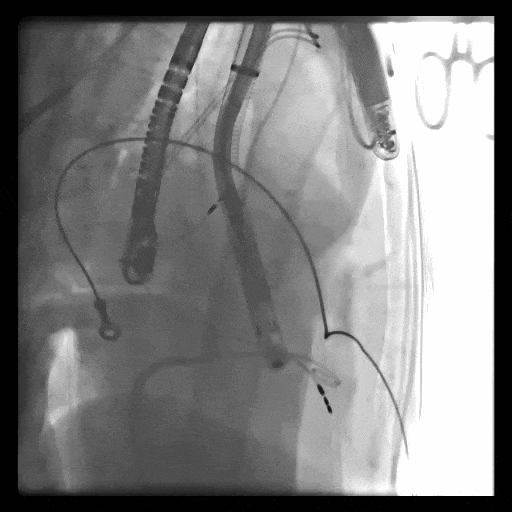

1、血管入路問題,最窄處平均徑5.5mm(小于8.5mm),輸送器存在進入受阻礙風險; 2、投照體位過大,RAO76°,術中影響輸送器操作可能性大;3、三尖瓣環(huán)大,同軸性難調整,易產(chǎn)生瓣周漏;4、起搏器導線在三尖瓣瓣環(huán)中心位置穿過,且較短,可能限制人工瓣膜展開,且尖端靠近室間隔錨定區(qū),可能影響錨定;5、三尖瓣極重度反流,藥物不能緩解患者的癥狀,在應用LuX-Valve Plus之前,心臟專家經(jīng)長時間評估均未為患者找到合適的產(chǎn)品或治療方案。

術中DSA顯示起搏器導線的干擾,右心室造影確定瓣環(huán)位置,操作空間小